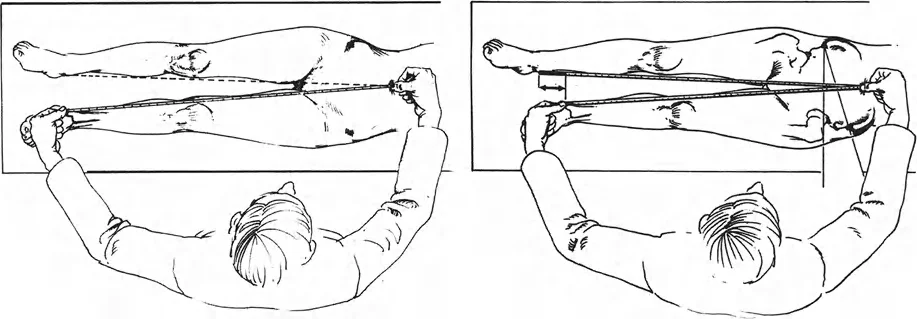

اختبار الكتلة الواقفة (The Functional Block Test):

توجد العديد من المنهجيات لقياس تفاوت الطول سريريًا، ولكن الأكثر أهمية وظيفيًا هو اختبار الكتلة الواقفة. يمتلك معظم المرضى إحساسًا عميقًا بتفاوت طول أطرافهم. من خلال جعل المريض يقف حافي القدمين على سطح مستوٍ وثابت، ووضع كتل خشبية أو بلاستيكية معايرة ذات سمك معروف تحت الطرف الأقصر، يمكن للجراح تقييم التفاوت الوظيفي بدقة.

يمثل ارتفاع الرافعة المطلوبة لتسوية الحوض (خاصة محاذاة عرف الحرقفة والشوكات الحرقفية الخلفية العلوية) وجعل المريض يشعر بأن أطرافه متساوية الطول، تفاوت الطول السريري المهم.

من الأهمية بمكان ملاحظة أن تفاوت الطول طويل الأمد غالبًا ما يؤدي إلى آليات تعويضية، بما في ذلك ميلان الحوض الثابت، وتقلص الكاحل الانقلابي (Equinus contracture)، والجنف القطني التعويضي. في المرضى البالغين الذين عاشوا مع تفاوت لعدة عقود، قد يؤدي تحقيق المساواة الرياضية (التصحيح الهيكلي الكامل لتفاوت الطول) إلى شعورهم بأن الطرف الذي تم تطويله حديثًا أطول مما يجب. يُعد اختبار الكتلة أمرًا بالغ الأهمية لأنه يكشف عن التصحيح المقبول، والذي قد يختلف بشكل كبير عن التصحيح الإشعاعي. -